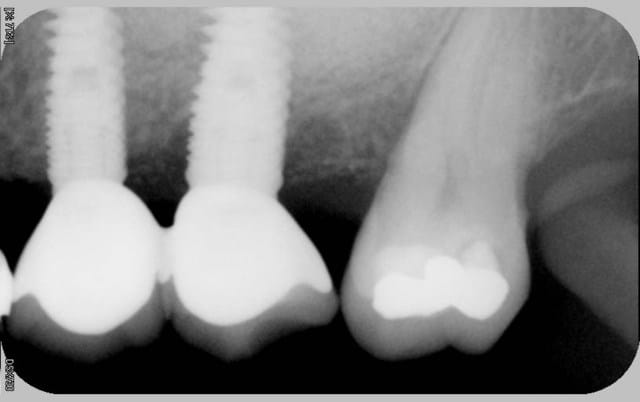

comme promis

voici les cas vus ce mardi (il me manquait encore 10 patients: sur les 5 autres, tout est ok)

ps: la carie et le tartre sur la 7 ont été traités